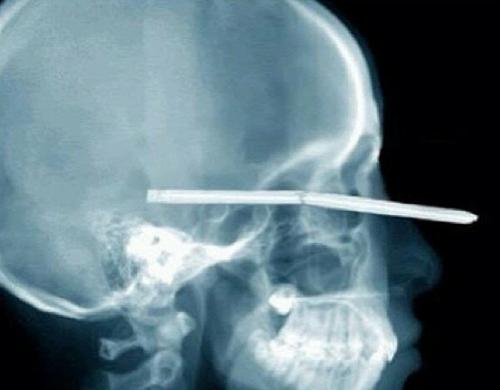

Повезло человеку — выжил